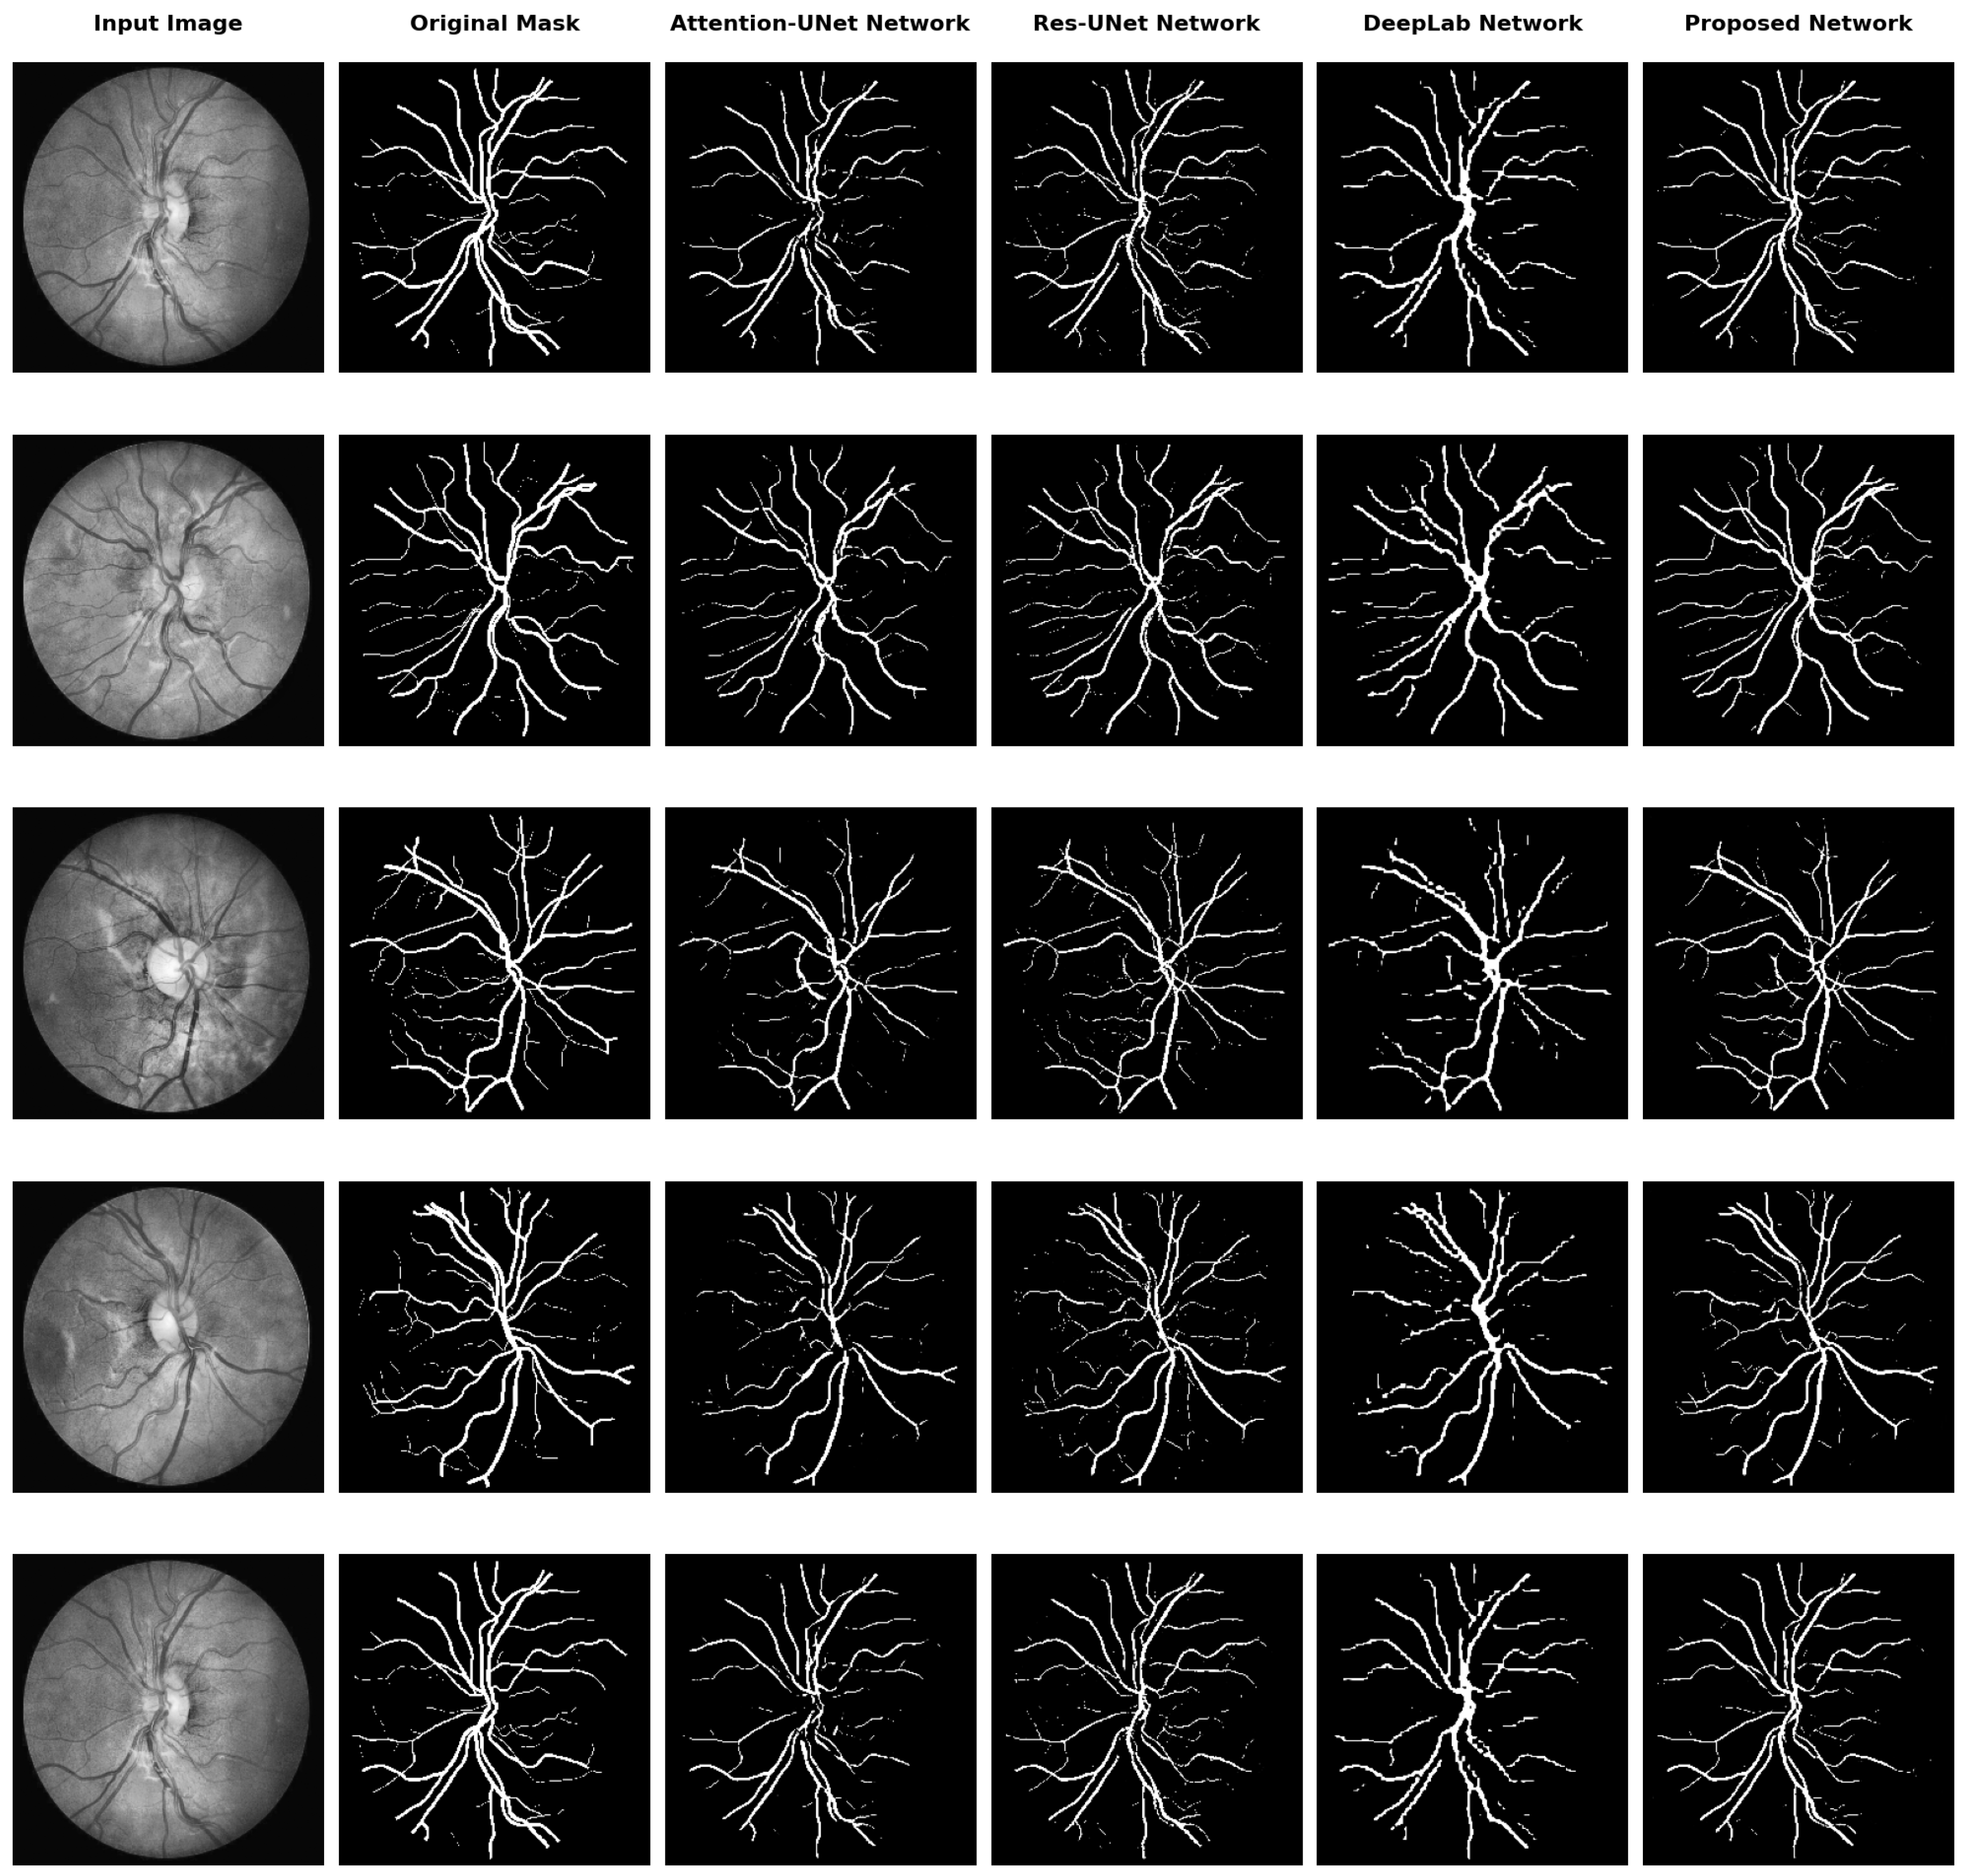

Additionally, we conducted a visual comparison of segmentation results obtained from different baseline models and our proposed model. Figure 3 illustrates the segmentation outputs for five different input retinal images from the CHASEDB1 dataset. Meanwhile, Figure 4 illustrates the segmentation outputs for two different images from the ISO-STAR, HRF, and LES-AV datasets. The results from Attention U-Net, ResU-Net, DeepLabv3+, and our proposed model are compared side by side.

Significant variations in vascular connection and continuity across the various baseline models can be seen upon visual evaluation of the segmentation data. For example, DeepLab has poor vessel-to-vessel connection, leading to discontinuous and fragmented vessel segments. This is explained by the DeepLab architecture’s intrinsic constraints in capturing the contextual data and long-range dependencies required to keep vessels connected.

Even while vessel connectedness is better than in DeepLab, as demonstrated by the segmentation results from Attention U-Net, ResU-Net, and our suggested model, there are still some vessel fractures and discontinuities. Obstacles like vessel overlap, low contrast areas, or noisy image artifacts can cause these gaps and compromise the precision of segmentation algorithms.

Figure 4. Qualitative analysis of the proposed network and its comparison with existing segmentation baseline models on ISO-STAR, HRF, and LES-AV datasets.